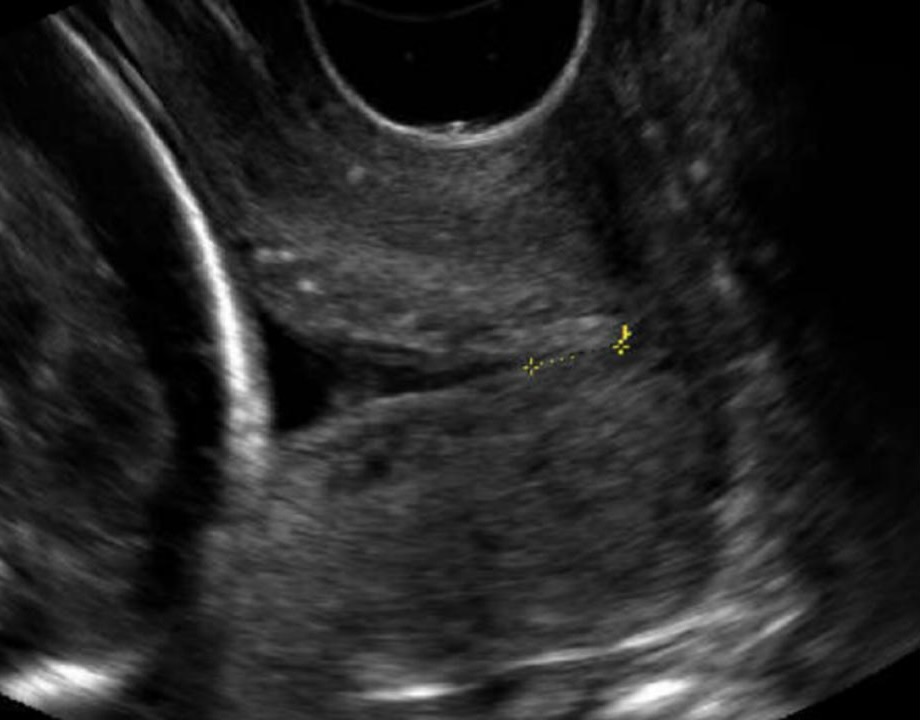

4. Accurately determining cervical funnelling

The key to deciding whether there is actually cervical funnelling is to assess whether the membranes bulge into the cervical canal. With true cervical funnelling the membranes will always bulge into the cervical canal.

Figure 2b. Example of short cervix with evidence of cervical funnelling. Note the membranes forming a V-shape into the cervical canal